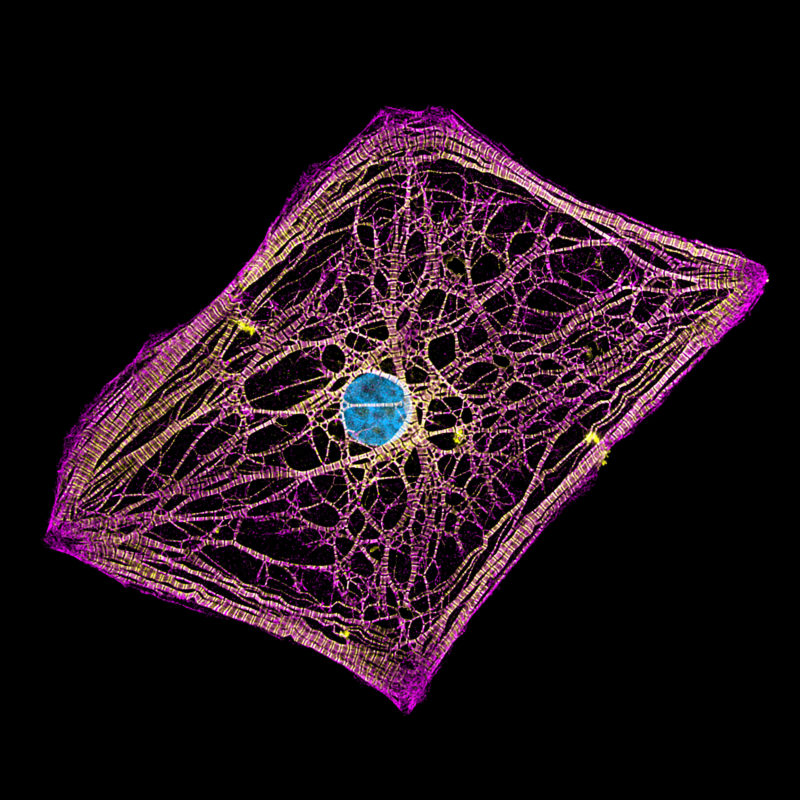

Image Analysis Technique Provides Better Understanding Of Heart Cell

https://publishing.aip.org/wp-content/uploads/2020/05/JAP19-AR-05841_image-scaled.jpg